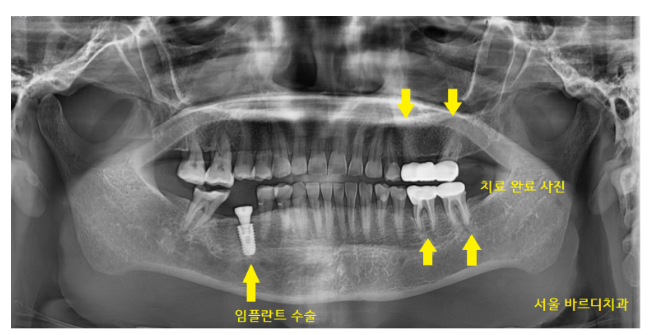

240328

보철 머리를 만들어드린 사진입니다.

전신질환이 많으셨지만

협진 진료

수술 후 충분한 휴식으로 컨디션 관리를 해드렸더니

치료 마무리까지 무사히 끝낼 수 있었습니다.